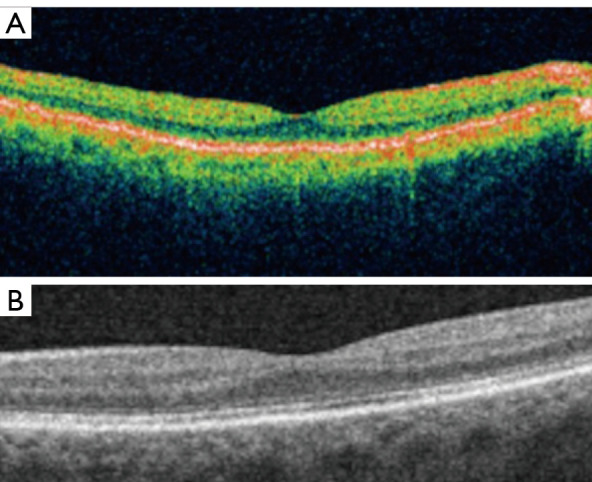

Background and objective: Optical coherence tomography (OCT) is a non-invasive imaging tool that can provide rapid cross-sectional images of the retina, cornea, and optic nerve head in live patients. The objective of this review is to provide an overview of the technical advancements and current clinical applications of OCT for managing patients with retinal disorders.

Key content and findings: Unlike the first-generation time-domain OCT (TD-OCT) instruments, the newer spectral-domain OCT (SD-OCT) instruments use a broadband light source to increase axial image resolution. In addition, the decreased image acquisition time also increases the transverse image resolution, reduces motion artifacts, and allows serial cross-sectional images of the retina to be obtained rapidly. A three-dimensional (3D) image of the retina, reconstructed using serial two-dimensional (2D) OCT images, can be used to quantitate retinal thickness and volume and perform analysis of retinal topography. Currently, commercial SD-OCT instruments are used routinely in clinical practice to obtain morphologic information used to diagnose and manage patients with various retinal disorders including macular degeneration and diabetic retinopathy. Newer swept-source OCT technology with faster image acquisition, provides wider field imaging of the peripheral retina. SD-OCT instruments can be incorporated into surgical microscopes to allow imaging of the retina during retinal surgery so that morphologic changes in the retina from surgical maneuvers can be observed in real time. More recently, OCT angiography (OCTA) has been developed which allows rapid, non-invasive 3D imaging of retinal and choroidal vascular flow. This is achieved by processing rapid serial SD-OCT images to detect movement of blood cells within vessels. Research has been done to further improve image resolution of SD-OCT to a cellular level by adding adaptive optics (AO) technology. The latest in SD-OCT technology is optoretinography (ORG), a technique to derive functional information from OCT images of the retina.

Conclusions: Advancement in OCT technology has made it possible to obtain high resolution retinal images that can provide anatomic, physiologic and functional information of the retina in live patients.